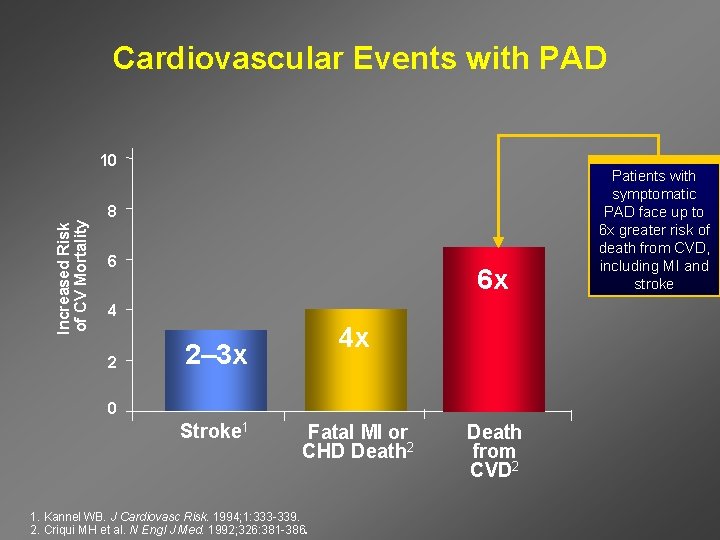

Cardiovascular Events with PAD Increased Risk of CV Mortality 10 8 6 6 x 4 2 4 x 2– 3 x 0 Stroke 1 Fatal MI or CHD Death 2 1. Kannel WB. J Cardiovasc Risk. 1994; 1: 333 -339. 2. Criqui MH et al. N Engl J Med. 1992; 326: 381 -386. Death from CVD 2 Patients with symptomatic PAD face up to 6 x greater risk of death from CVD, including MI and stroke